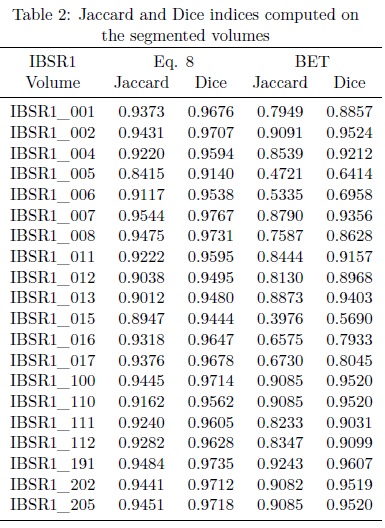

In Fig. 9 some output images belonging to the volume IBSR_7 (see Fig. 9(a)) and processed with the algorithm aforementioned are exhibited, see Fig. 9(c). In order to compare our results, the Jaccard and Dice indices are computed on: i) manual segmentations obtained from the IBSR volumes, and ii) segmentations obtained from the BET algorithm implemented in the MRicro software with default parameters.

Some slices of the manual segmentation corresponding to the volume IBSR_7 are presented in Fig. 9(b), while a set of slices belonging to the volume segmented with the MRicro software are displayed in Fig. 9(d). The Jaccard and Dice indices associated to the aforementioned segmentations are presented in Table 2.

According to the computed indices, the Eq. 8 outperforms the BET algorithm. However there are some points to mention:

1. BET algorithm is faster and only requires 2 seconds to segment the volume. Nevertheless, during the segmentation of the brain, this is cropped like a circle, due to this, the Jaccard and Dice indices have minor values than those computed with Eq. 8.

2. The proposed algorithm utilizes 83 seconds to segment a brain with 60 slices, and although the time is superior to the BET algorithm, the segmentations are better. In 12, the maximum time reported for other methodologies to separate brain is 35 minutes. Also in [12], two expressions to segment brain are proposed, the Eq. 9 and Eq. 12. The results obtained in this paper outperform those obtained with Eq. 12 and the reduction of the execution time is considerable. Our algorithm utilizes 83 seconds while Eq. 9 and Eq. 12 employ 174 and 354 seconds to process a volume of 60 slices respectively.